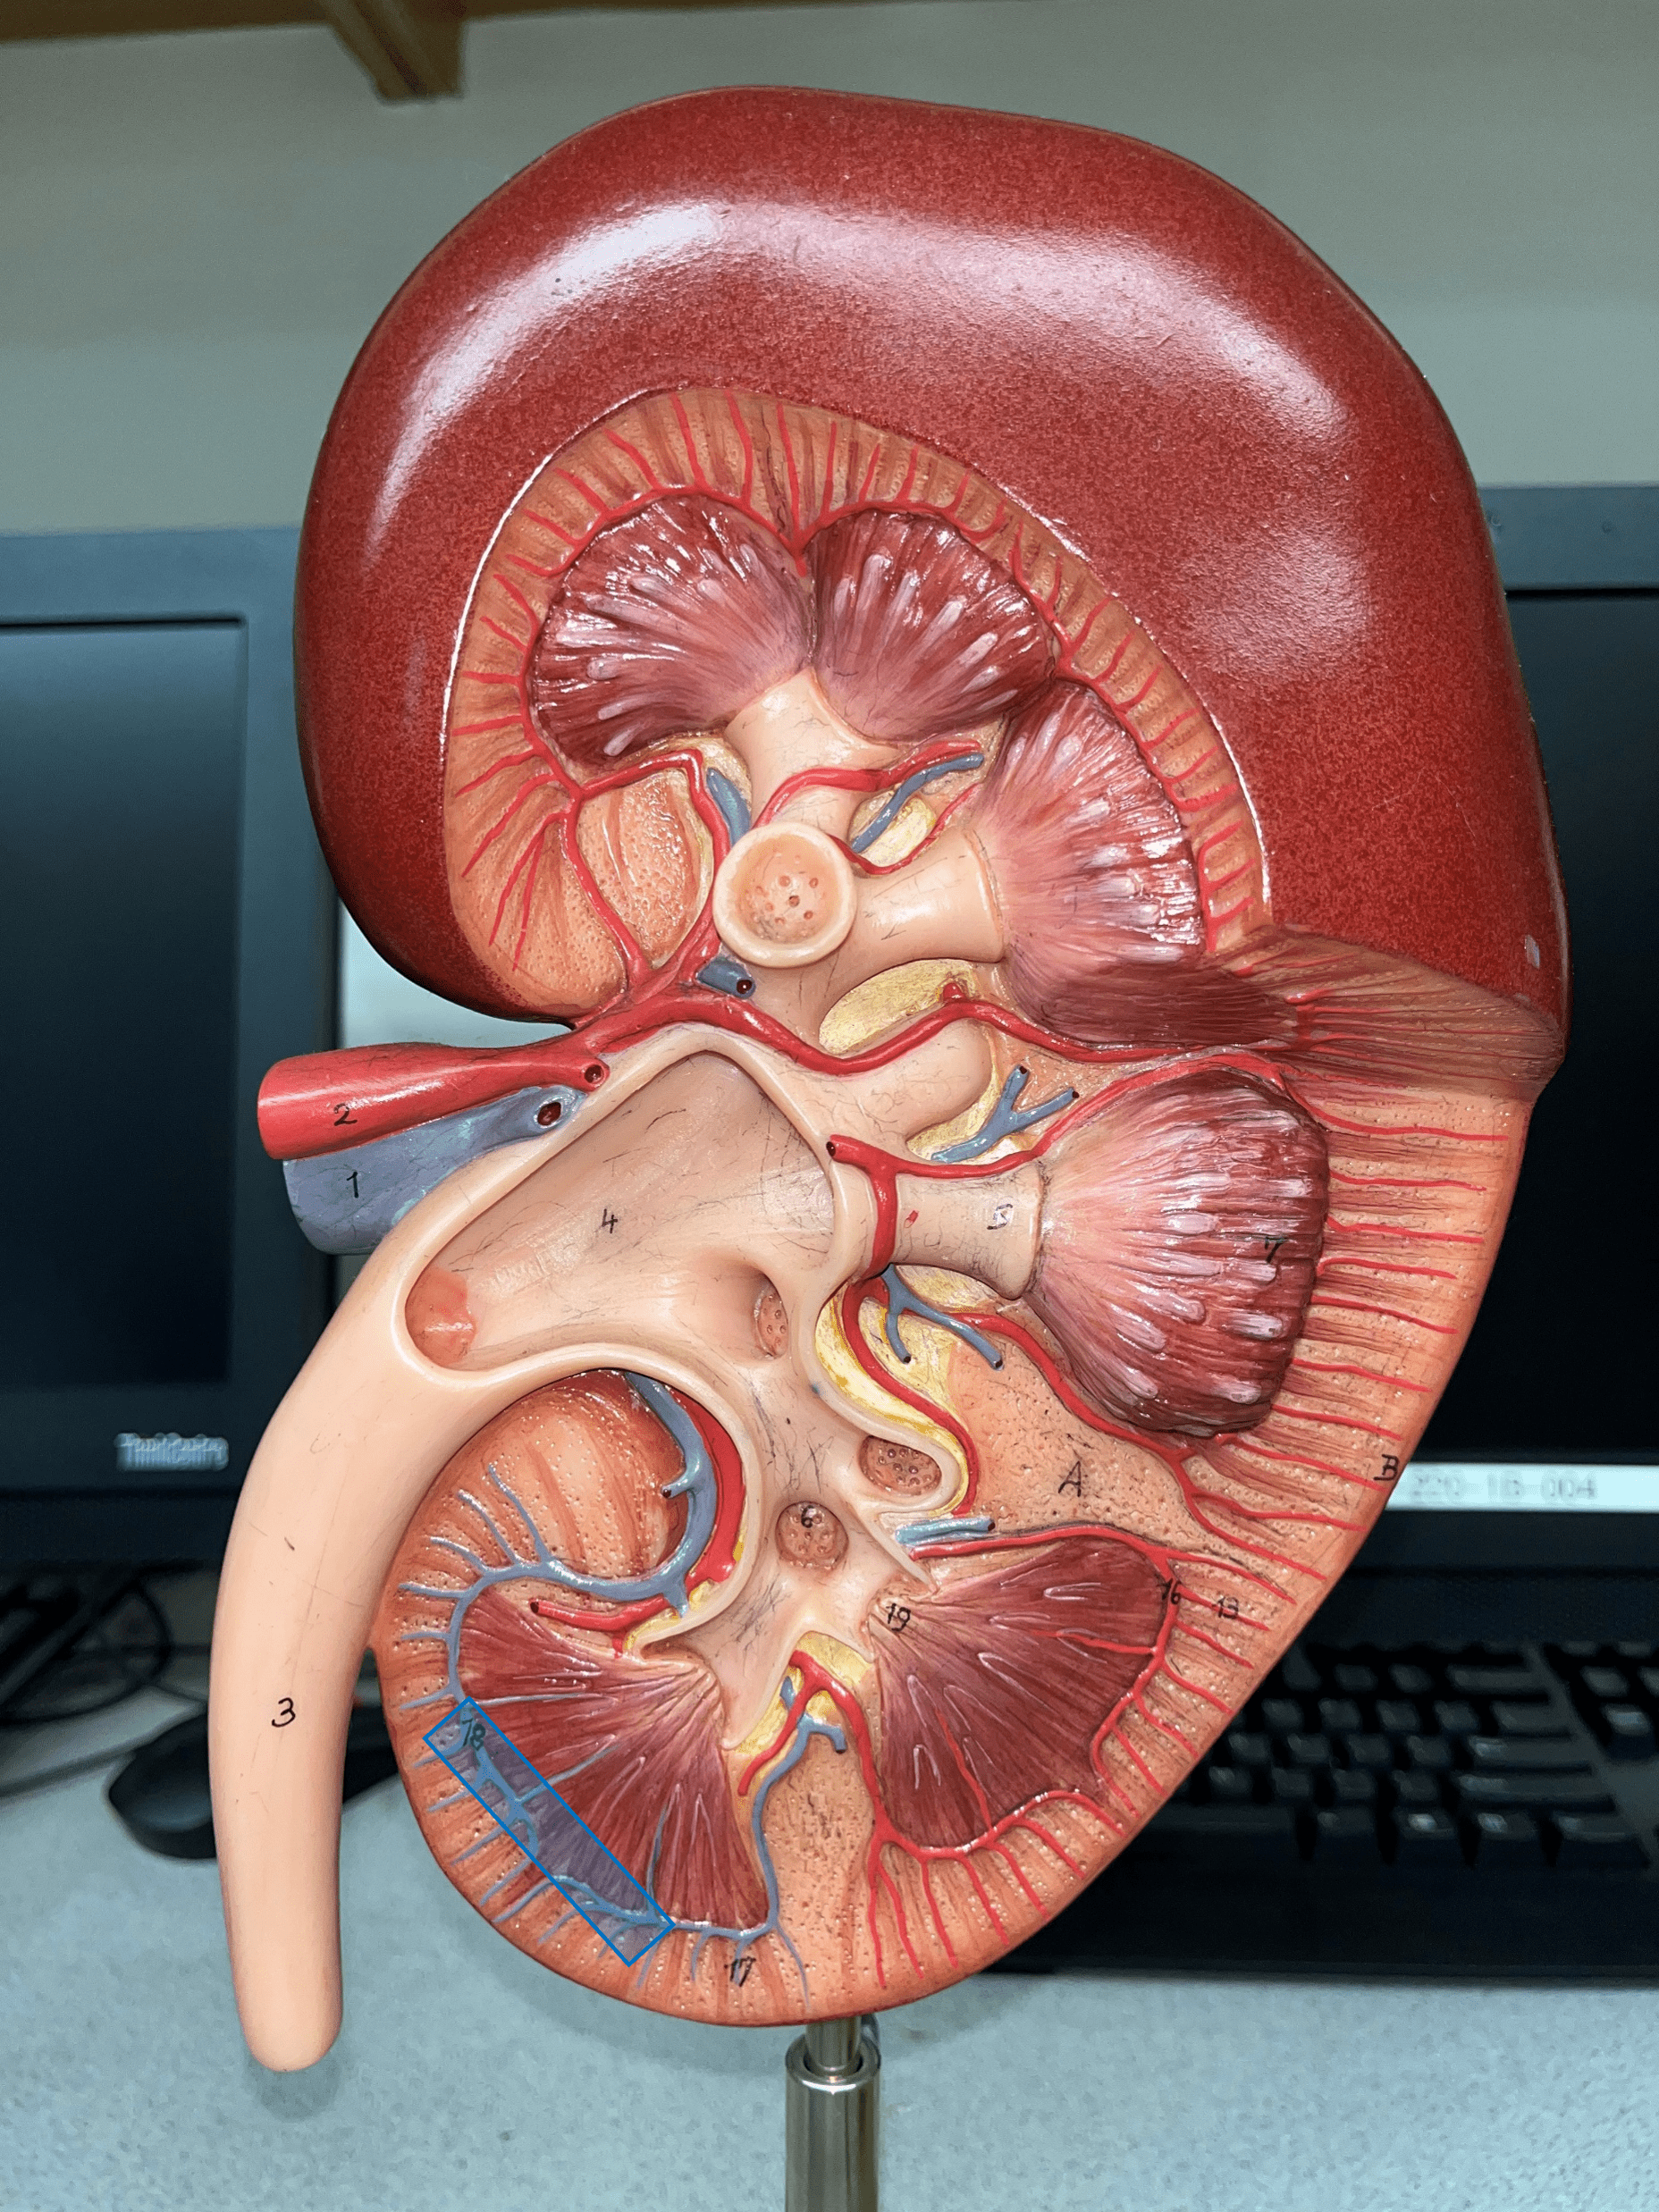

interlobar artery

arcuate artery

interlobular artery

interlobular vein

arcuate vein

interlobar vein

renal pyramid

renal medulla